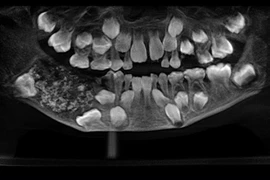

(Kiến Thức) - Các chuyên gia khuyến cáo rằng, kiểm tra răng miệng định kỳ có thể giúp phát hiện bệnh sớm. Nếu được điều trị kịp thời, hiệu quả sẽ tăng lên rất nhiều.